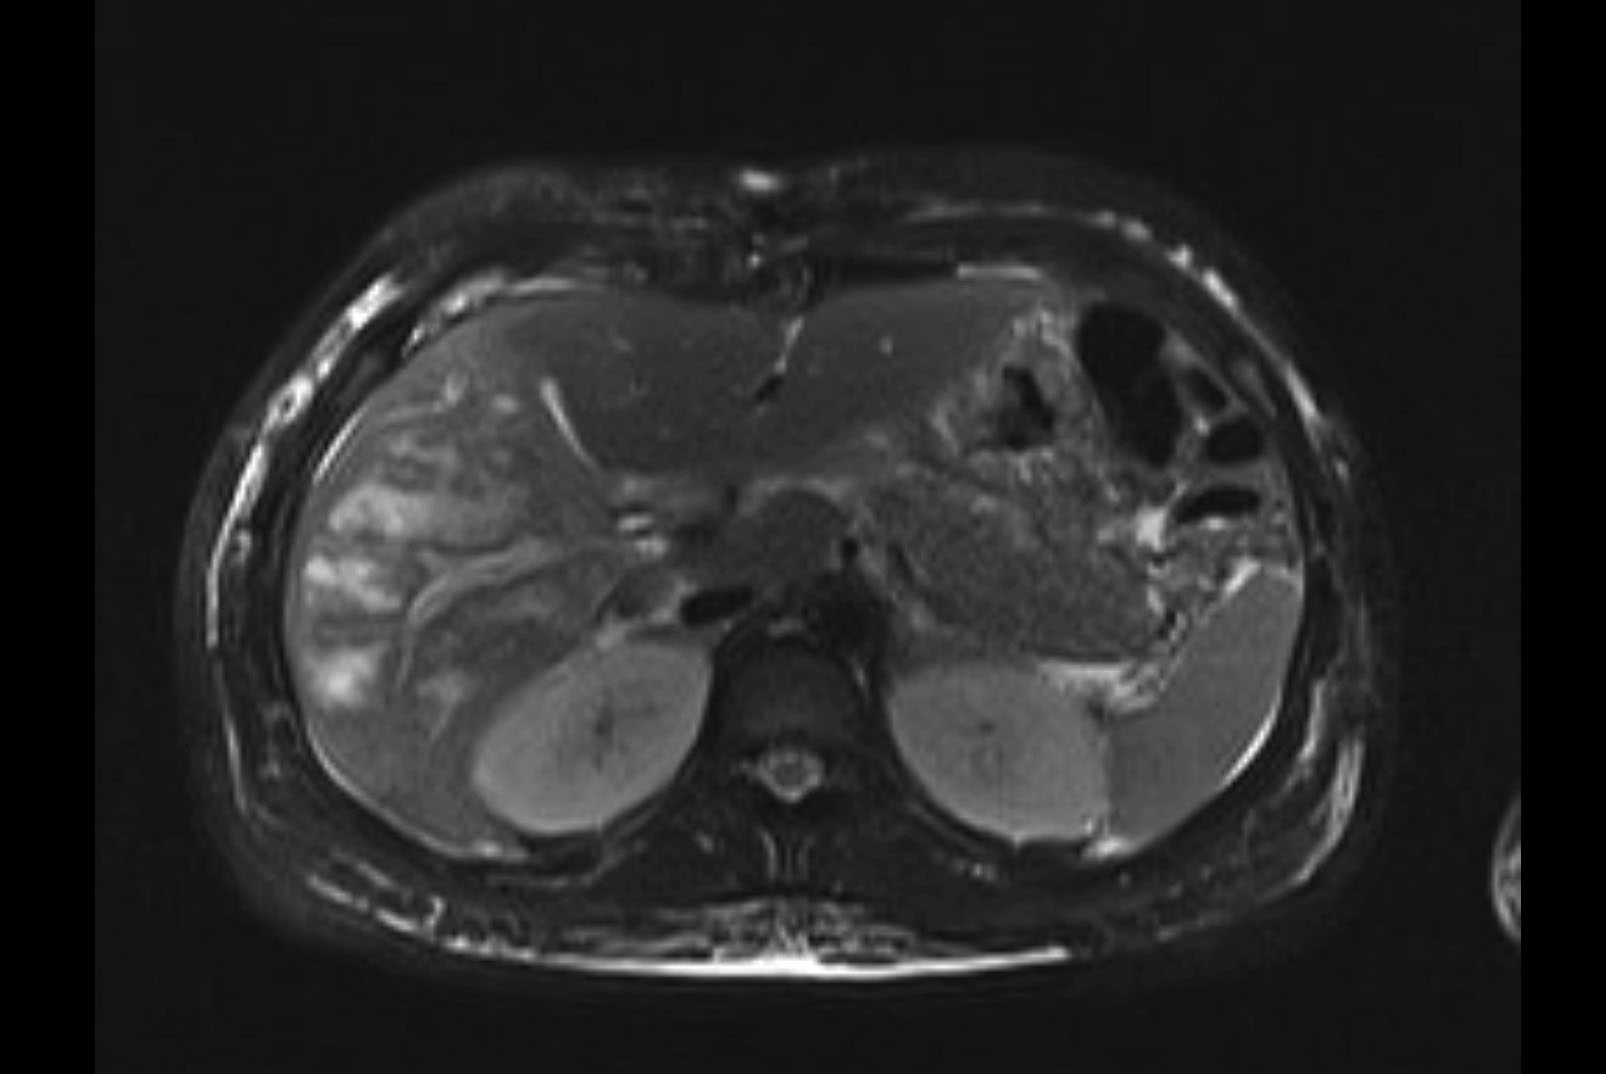

MRI T1

MRI T2